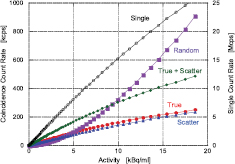

Figure 7 shows the total count rate capability of the system for true, random, and scatter coincidence events, including single events, as a function of the line source activity divided by the total volume of the cylindrical phantom. These data were corrected by subtracting the 176Lu background count rate of 415 cps and 381 cps for the prompt (T + S) and random coincidence rate, respectively, whereas the single background count rate was 520 kcps. The true count rate reached 249 kcps, and seemed to continue to increase. The single count rate also increased over 25 Mcps, suggesting that the dead-time losses were slight. This indicates that the single-event data acquisition system worked well even in the high-count rate regions. The NECR_1R and 2R are shown in figure 8. The peaks of NECR_1R and 2R were 44.7 kcps at 17.5 kBq ml−1 and 27.9 kcps at 11.9 kBq ml−1, whereas SF was 48.3% and 47.2%, respectively.

Figure 7. Count rate capability as a function of the line source activity divided by the total volume of the 70 cm cylindrical phantom.

Download figure:

Standard image High-resolution imageFigure 8. Noise equivalent count rate (NECR) as a function of the line source activity divided by the total volume of the 70 cm cylindrical phantom.

Download figure: